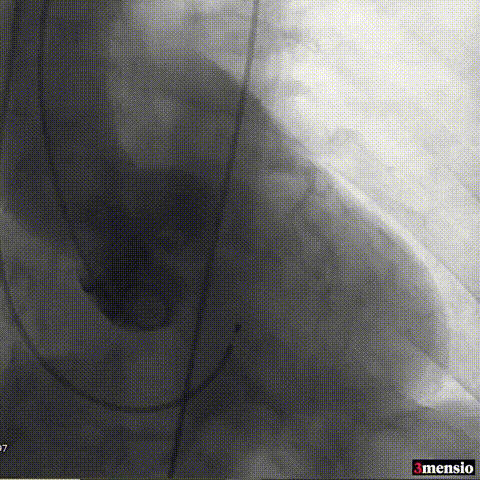

图片

主动脉根部造影

导丝跨瓣